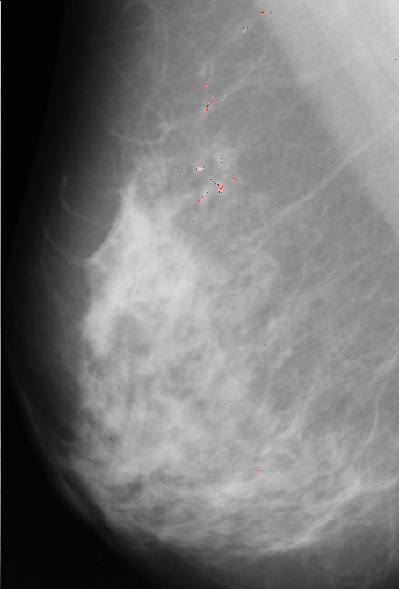

Template, multiplied with pixel value at current position, is substracted from median filtered image. The results are normalized, thresholded and added to

original image to point to possible position of microcalcification.

A result of this approach is: